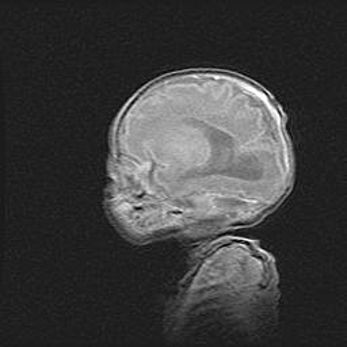

Мальформация Денди-Уокера. Киста задней черепной ямки.

Агенезия мозолистого тела.

Возраст: 2,5 месяца

Вес: 2420 г

Пол: женский

Окружность головы: 37 см

Срок гестации: 32 недели

Мальформация Денди—Уокера — редкий вид патологии ЦНС, представляющий собой врожденный порок развития каудального отдела ствола и червя мозжечка, ведущий к неполному раскрытию срединной (Мажанди) и латеральных (Лушка) апертур IV желудочка мозга. Для этогно синдрома характерна триада симптомов: гипотрофия червя мозжечка и/или полушарий мозжечка, кисты задней черепной ямки, гидроцефалия различной степени. В 70% случаев порок сочетается и с другими аномалиями головного мозга, в частности с агенезией мозолистого тела.